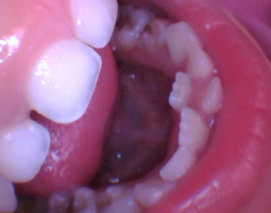

宝宝一般从6-7岁开始换牙,乳牙逐渐脱落,恒牙相继萌出。恒牙已经萌出,相应位置上的乳牙尚未脱落,叫做“乳牙滞留”。

1)常见下颌乳中切牙滞留,恒中切牙于舌侧萌出,呈现双排牙现象。继承恒牙已经萌出,滞留的乳牙应该拔除。